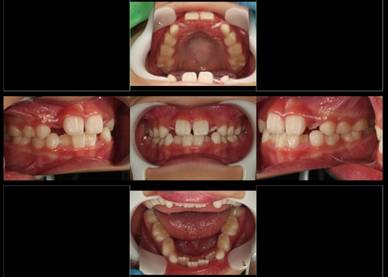

乳歯列の反対咬合がムーシールドで改善したケース

|

3歳

7歳 乳側切歯を抜歯しています

8歳 乳犬歯を抜きたいと希望されて来院。もう少し様子を見ることにしました